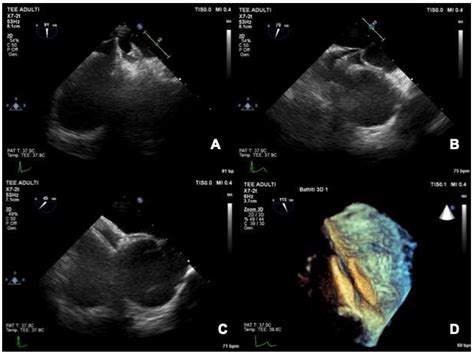

2408×2614

cvcasejournal.com

Three-dimensional Transesophageal Echocardio…